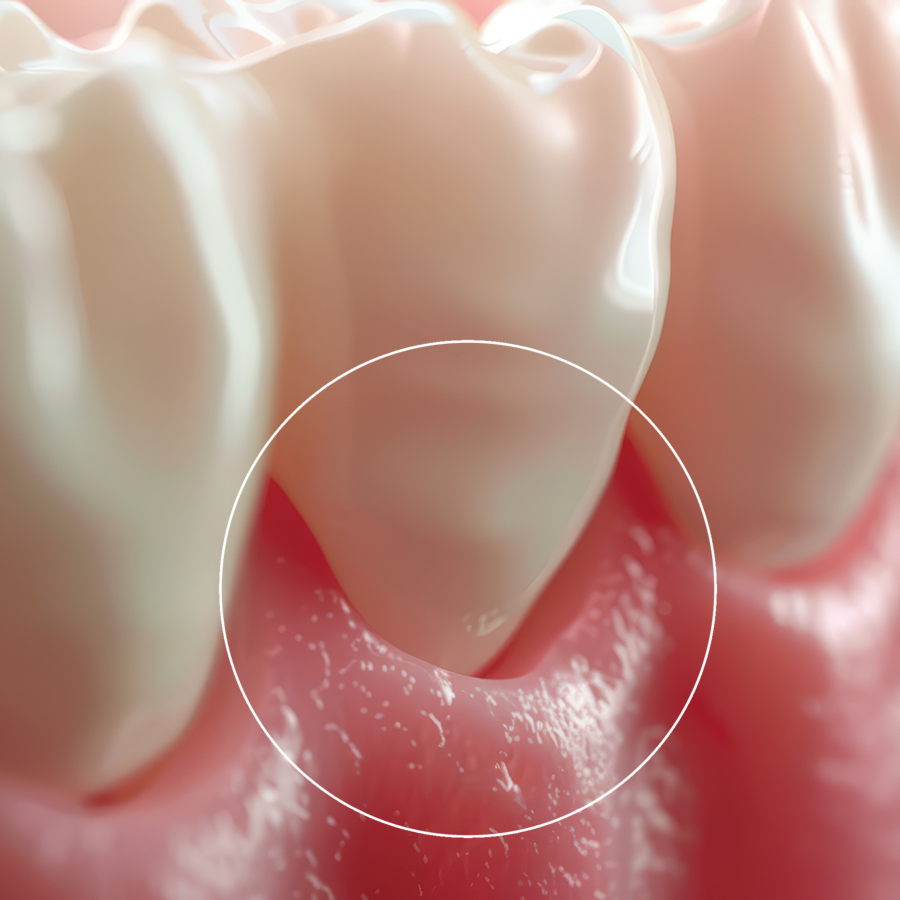

Η ουλίτιδα και η περιοδοντίτιδα είναι ιδιαίτερα συχνές παθήσεις και συχνά εξελίσσονται χωρίς έντονα συμπτώματα. Αν δεν αντιμετωπιστούν έγκαιρα, μπορεί να οδηγήσουν σε αιμορραγία, κακοσμία, υποχώρηση ούλων και απώλεια δοντιών.

Φλεγμονή των ούλων με σημεία όπως αιμορραγία, ερυθρότητα και ευαισθησία. Αν διαγνωστεί έγκαιρα, αντιμετωπίζεται πλήρως.

Προχωρημένο στάδιο φλεγμονής που προσβάλλει τους ιστούς στήριξης των δοντιών και απαιτεί εξειδικευμένη και συστηματική θεραπεία, προσαρμοσμένη στις ανάγκες κάθε ασθενούς.